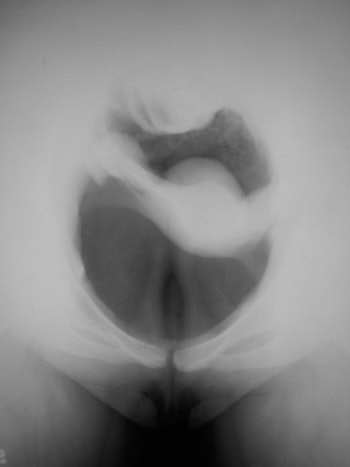

Diagnostic pneumoperitoneum/gynecography

In this technique, an abdominal radiograph is made following the induction of a pneumoperitoneum, and was developed by Eugen Weber from Kiev, Ukraine, in 1912. A specifically gynecological use was described by Otto Goetze from Halle, Germany, in 1918. The patient was placed head down and prone, and a pelvic radiograph was obtained with the pelvic viscera outlined with air. The uterus, bladder, and ovaries could be identified, and the bowel would fall out of the pelvis. Goetze said that he used the technique to diagnose pregnancy in the early months, infantilism, myomata, uterine and adnexal adhesions, pyosalpinx, and ovarian tumors. The patient illustrated below was examined in 1967 and the examination was normal. This was just before the introduction of ultrasound, which rendered the examination obsolete.